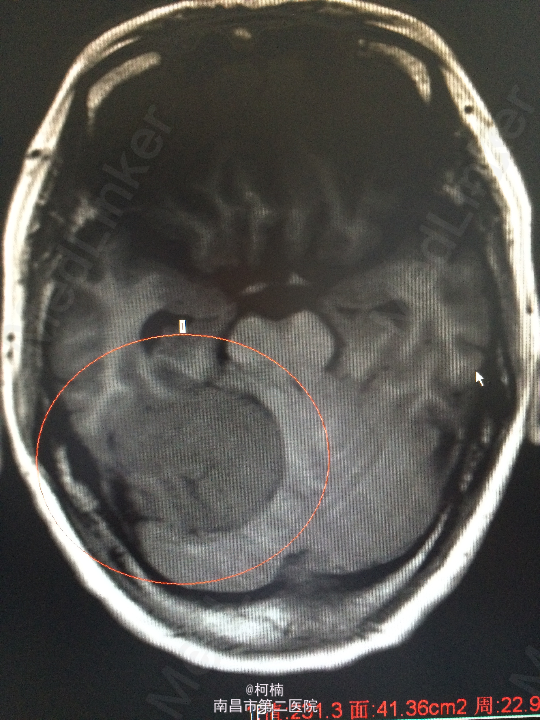

主诉:反复头晕、头痛伴呕吐及行走不稳10月余 病史:患者老年女性,55岁,10余月前开始出现头晕、头痛伴呕吐及行走不稳,无肢体乏力、肢体抽搐、意识障碍等不适,于当地医院诊治行头颅MR提示:右侧小脑角占位,考虑肿瘤。 查体:神经系统体查未见明显异常

查体:神经系统体查未见明显异常 辅助检查:头颅MR提示右侧桥小脑区占位性病变,考虑脑膜瘤。四脑室狭窄,变形,幕上脑室积水,小脑扁桃体疝

诊断:右侧小脑脑膜瘤 处理:先行介入栓塞肿瘤供血动脉,再行开颅手术治疗,术后予组织病理检查,提示:脑膜瘤

随访:术后患者症状缓解出院 讨论:脑膜瘤(Meningiomas)是起源于脑膜及脑膜间隙的衍生物,发病率占颅内肿瘤的19.2%,居第2位,女性:男性为2:1,发病高峰年龄在45岁,儿童少见。许多无症状脑膜瘤多为偶然发现。多发脑膜瘤偶尔可见,文献中有家族史的报告。50%位于矢状窦旁,另大脑凸面,大脑镰旁者多见,其次为蝶骨嵴、鞍结节、嗅沟、小脑桥脑角与小脑幕等部位,生长在脑室内者很少,也可见于硬膜外。其它部位偶见。手术为其首选的治疗方案。